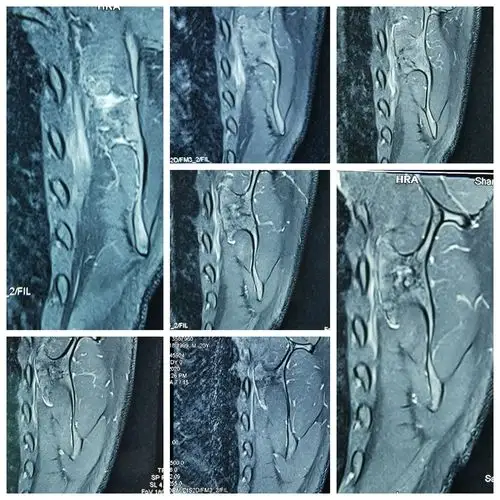

肩膀疼痛原因探秘系列之:介绍一肩关节后侧疼痛肩胛骨下半部骨巨细胞

一例肩胛骨 [病例帖]

术前mri检查结果提示:肩胛骨良性肿瘤可能性大.

左肩胛骨病变